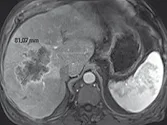

Figure 3. Métastases hépatiques d’un cancer du colon.

A. Examen initial montrant que le grand axe de la lésion est de 81 mm.

B. Après quatre cycles de chimiothérapie, la lésion mesure 59 mm, soit une amélioration de 27 %. Bien que la lésion ait visuellement diminué de façon évidente, il ne s’agit pas encore d’une réponse partielle, car le cap des 30 %

de diminution n’est pas franchi. La réponse est classée « SD »